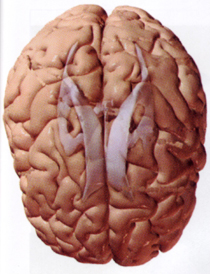

Waren Neurolipide früher natürlicher Bestandteil unserer westlichen Ernährung, vielerorts sogar eine Delikatesse, fehlen sie heute auf dem Speiseplan. Es gab unterschiedliche Rezepturen zur Zubereitung von Hirnprodukten. Typische Wurstprodukte, die Hirn enthielten, waren in Norddeutschland die Bregenwurst, in Bayern die Weißwurst. Damit waren die notwendigen Lipide aus Hirn, Rücken- und Knochenmark in unserer Ernährung präsent. Neurolipide enthalten Trillionen spezifischer Lipidmoleküle. Diese haben unterschiedlichste Wirkung auf die Gesundheit. Ihr Fehlen in der Nahrung kann zu Mangelkrankheiten führen. Neurolipide sind verantwortlich für den Aufbau und die Regulation unseres zentralen Nervensystems und zwar von der Embryogenese bis ins hohe Alter. Sie sorgen für eine adäquate Entstehung des embryonellen Gehirns, besonders in den ersten 3 Monaten der Schwangerschaft. Nach Tallberg (Prof. Dr. Thomas Tallberg, Tumorbiologe, Helsinki, Anm. d. Redaktion) beruht das Schwangerschaftserbrechen auf einem Mangel an Neurolipiden in der Nahrung der Mutter, die der Embryo zum eigenen Hirnaufbau benötigt. Bei heranwachsenden Embryos entstehen bei ausreichender Neurolipidversorgung optimal funktionierende Nervenendplatten. Diese sorgen für eine geordnete und harmonische Übertragung von Nervenimpulsen untereinander und zu den Muskeln.

Neurolipide sind nach Tallberg mitverantwortlich für die mentale u. motorische Balance sowie Konzentration.

Weiterhin steürt sowohl beim Heranwachsenden, als auch beim Erwachsenen das ZNS mit Hilfe der Neurolipide permanent die Zellneubildung und Zellregeneration. Tallberg nimmt an, daß darüber hinaus ein Schutz vor Krebsgenen besteht.